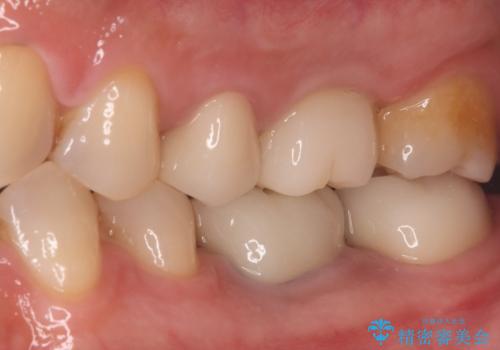

オールセラミックによる修復: 天然歯のような光の透過性と硬さを持つオールセラミックを使用しました。奥歯であっても、患者様固有の歯の色調や咬み合わせの溝を忠実に再現した修復物を装着。金属を一切使用しないことで、金属アレルギーのリスクを排除し、歯肉の色が黒ずむ心配もなくなりました。

【治療の結果】 全ての銀歯が白くなったことで、お口の中がパッと明るくなりました。見た目の美しさだけでなく、表面が滑らかなセラミックはプラークが付着しにくいため、将来的な虫歯や歯周病の予防効果も高まった健康的な口腔環境が実現しました。